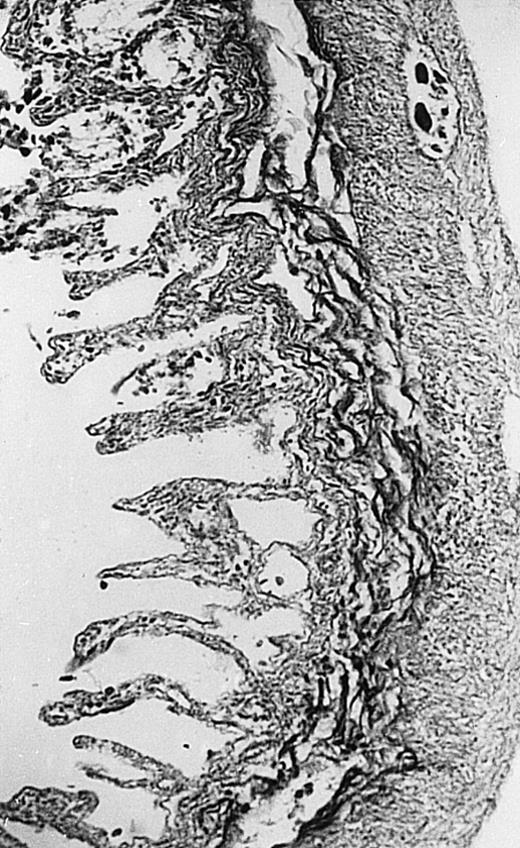

Pathologic findings in the small and large intestine were strikingly different depending on the treatment group. Figure 2A shows a representative pathologic sample from an animal assigned to the control group. Marked thinning of the bowel wall and extensive areas of epithelial cell sloughing was noted. Animals randomized to rhG-CSF treatment had minimal improvement in histologic findings with focal regions of preserved epithelium (Fig2B). Animals randomized to the rhIL-11 group showed substantial improvement with thickening of the epithelial layer and preservation of mucosal cell integrity (Fig 2C). Animals receiving both rhG-CSF and rhIL-11 had the most favorable histologic findings with normal mucosal thickness, minimal inflammatory changes, and preserved tissue architecture (Fig 2D). The composite analysis of the gastrointestinal pathology is provided in Table 1.

Histopathology of small intestinal mucosa cut in transection from an animal in each treatment group (study day 8). The upper panel (row 1) is a low power view (original magnification × 57); the lower panel (row 2) is a high power view (original magnification × 144). Note the diffuse thinning and necrosis of the mucosa with sloughing of intestinal epithelial cells in the control animal (A). There is progressive recovery of the thickness of the mucosa, reduction in inflammatory changes, and improved epithelial architecture with rhG-CSF (B), rhIL-11 (C), and combination therapy with rhG-CSF+IL-11 (D).

rhIL-11 has been shown to have marked effects on gastrointestinal epithelial surfaces. rhIL-11 blocks apoptosis of epithelial cells exposed to radiation and chemotherapy in mice.22 rhIL-11 is protective in a variety of mucositis models and in models of intestinal inflammation.4,23,24 rhIL-11 has been shown to prolong the G-0 phase of growth of intestinal epithelial cells. The precise mechanism of action is not known, but it has been observed that rhIL-11 decreased pRB (retinoblastoma protein) phosphorylation (an important signaling event in cell cycling) within intestinal epithelial cells.32 rhIL-11 has protective effects on gastrointestinal mucosa in transgenic rats, which possess HLA-B27 antigens.4These animals develop an inflammatory colitis that is similar in many respects to human inflammatory bowel disease. rhIL-11 treatment in these animals decreases intestinal inflammation and chronic diarrhea. Based on these preclinical findings, rhIL-11 is currently in clinical trials in both inflammatory bowel disease and chemotherapy-induced mucositis.33 The remarkable capacity of rhIL-11 to protect the gastrointestinal mucosal integrity after chemotherapy is apparent in the current series of experiments (Fig 2).

The beneficial effects of rhIL-11 in the neutropenic rat model may be mediated by its activity as a hematopoietic growth factor, an antiinflammatory cytokine, or its ability to maintain gastrointestinal epithelial integrity.25,33 The results of the current study would favor rhIL-11 protective effects on the intestinal epithelium as the principal mechanism protection in these animals. Maintenance of the gastrointestinal barrier function should diminish the frequency of gut translocation-derived bacterial infection after chemotherapy-induced myelosuppression and epithelial injury.25 The remarkable preservation of membrane integrity found on the gastrointestinal pathologic samples, the reduced circulating levels of endotoxin, and the reduced bacterial load in organ cultures support a dominant role for epithelial protective effects by rhIL-11 treatment in this animal model.